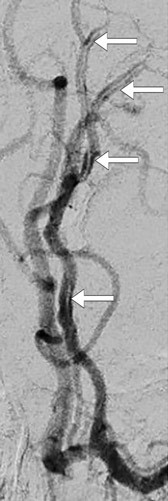

Cerebral MR dagen etter innkomst (bildet til venstre) viste infarktforandringer i mediale deler av venstre frontallapp, svarende til forsyningsområdet til venstre a. cerebri anterior, og MR-TOF-angiografi viste noe trombosering i A2-segmentet av arterien. Pasienten gjennomgikk omfattende utredning uten at man fant noen bakenforliggende årsak til infarktet. Etter to uker ble hun undersøkt med konvensjonell cerebral angiografi, som avdekket en disseksjon i A2-segmentet av venstre a. cerebri anterior (bildet til høyre). En måned senere var hun tilbake i full jobb, da var NIHSS-skår 0 (National Institute of Health Stoke Scale) og modified Rankin Scale (mRS) også 0.